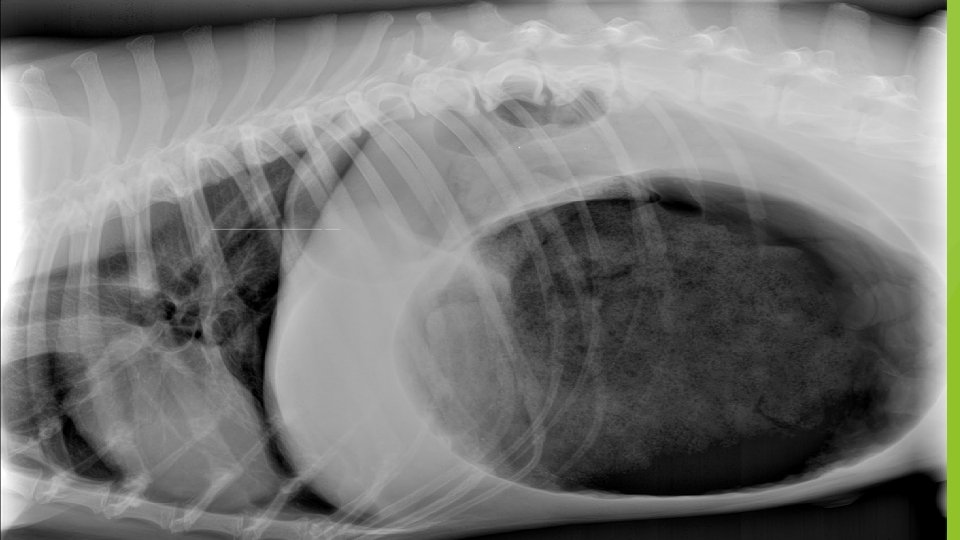

Gastric Dilation Clinical Signs Treatment Distension of the stomach – feels hard to touch and sound hollow when touched This is a genuine emergency and the animal must be seen ASAP Prepare theatre Discomfort and restlessness Dyspnea – the diaphragm is compromised The gas pressure of the stomach must be relieved by attempting to pass a stomach tube. A catheter may be placed into the stomach to release some of the pressure Treat for shock – IV fluids / TPR Collapse Shock – stomach pushes on major blood vessels

Ruptured Diaphragm Clinical Signs Treatment Torn diaphragm – if tear is small there may be no clinical signs Stabilise patient If the abdominal organs move into the thorax, the animal will show varying degrees of dyspnoea Place in warm quiet area If necessary, be prepared to administer oxygen Some animals may prefer to sit up right so that the abdominal contents fall downwards Allow the animal to adopt a position in which it feels most comfortable Severely affected cased mouth breath Observe TPR Withhold food prior to surgery Surgery required Low oxygen saturation

Diaphragmatic Rupture

Splenic Injuries Clinical Signs The spleen is a blood filled organ capable of profuse haemorrhage. Damage can be caused by tumours / trauma / torsion Sudden collapse Rapid RR Pale MM colour Blood filling in abdominal cavity If torsion – abdomen swollen and hard Treatment In cases where the spleen has ruptured very little can be done and the animal is likely to die of internal bleeding If the animal is able to be treated then treat for shock then surgery.

Splenic Removal